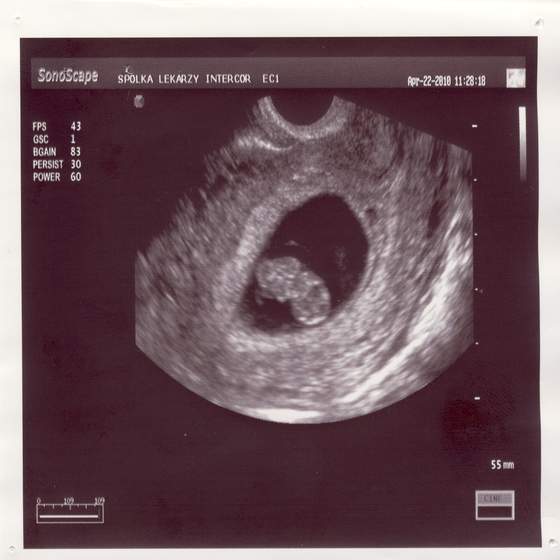

Byłam wczoraj u ginka i załączam Wam zdjatko małej 2 cm fasolinyjak widziałam bijące serduszko to się popłakałam....Zobacz załącznik 238861